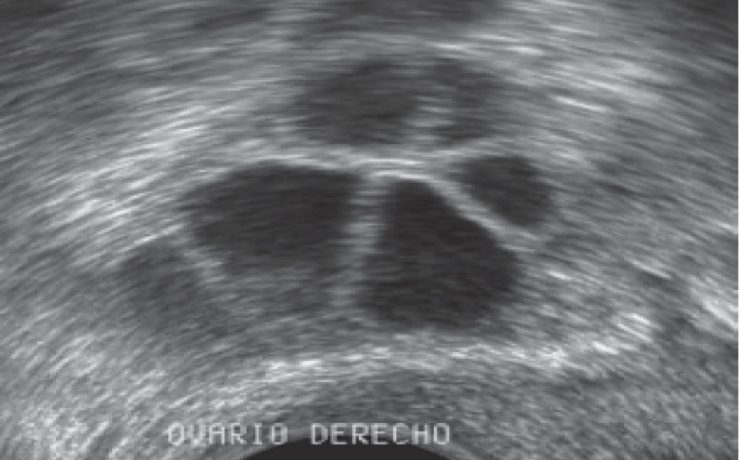

El diagnóstico de tumores ováricos durante el embarazo es cada vez más frecuente como consecuencia del mayor uso rutinario del ultrasonido desde etapas tempranas de la gestación. Si bien la frecuencia sigue siendo baja en relación con otras neoplasias asociadas al embarazo, se reporta una incidencia menor de 5%. Casi